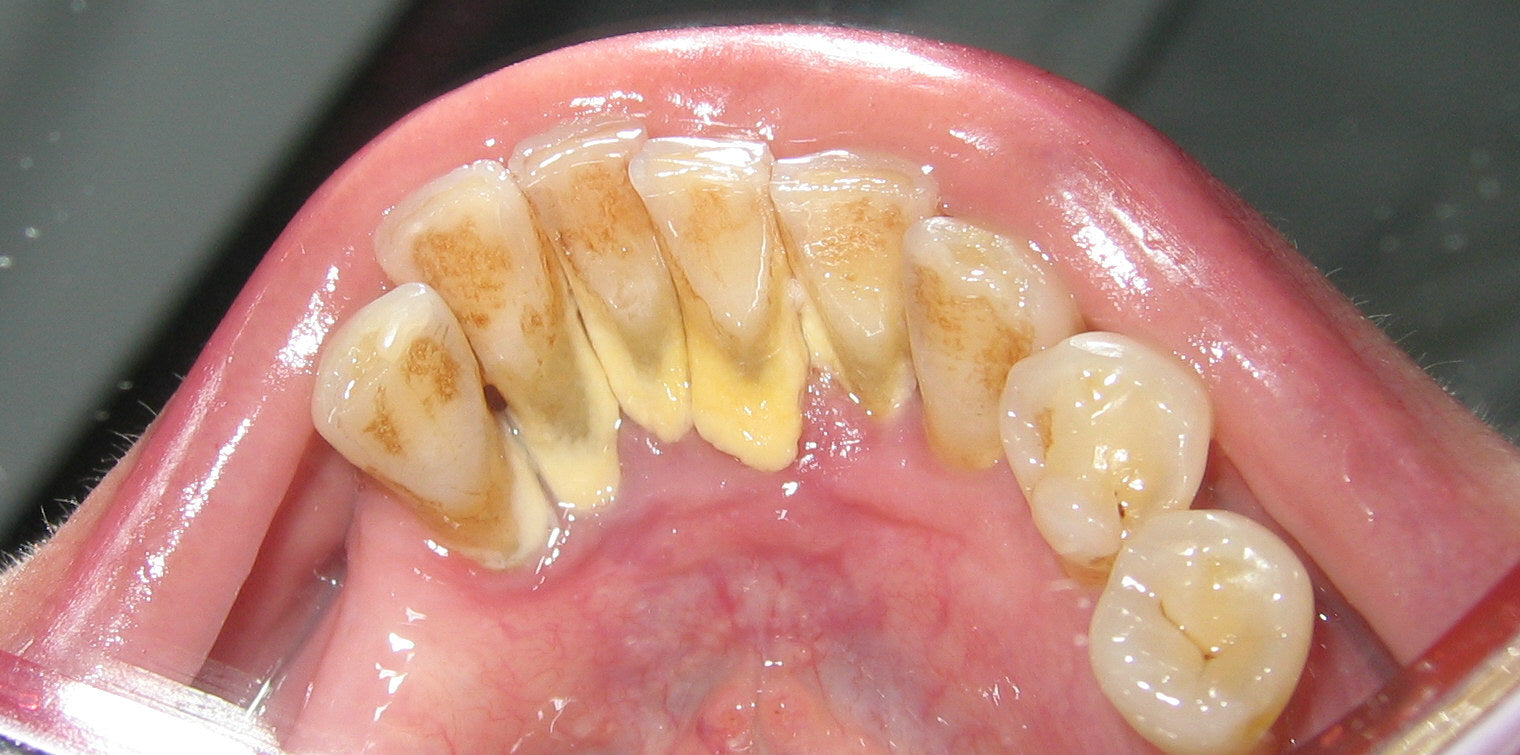

Tartar Buildup Can Become Severe Enough That People Stop Recognizing It as “Normal”

In my work as a dental hygiene professional, I’ve seen tartar buildup progress to a point where patients are genuinely surprised when they’re shown what’s happening along their gumline.

What often begins as light surface plaque can gradually harden and accumulate, changing the appearance of the teeth and gums over time. Because this happens slowly, many people don’t realize how significant the buildup has become until it’s clearly visible.

It wasn’t until earlier this year, while reviewing patient cases and current oral care practices, that I began to look more closely at why this pattern keeps repeating — and whether it could be addressed earlier, before reaching this stage.